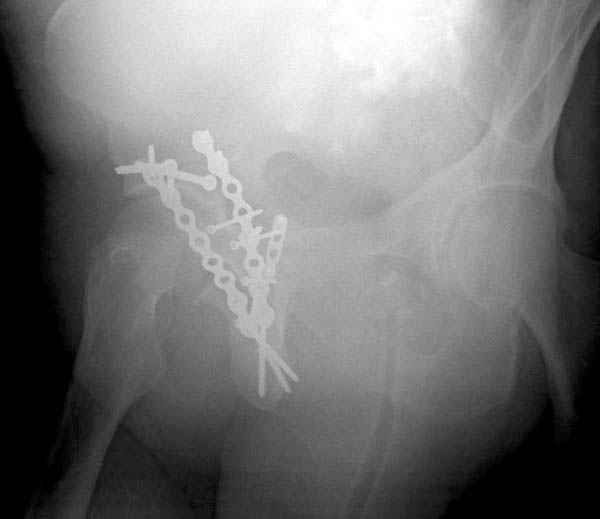

Дополнительно имеется перелом ацетабулума: задняя

колонна с полупоперечным переломом, и переломы костей лица.

На седьмой день зафиксирован перелом ацетабулума через задний доступ. Перед операцией для профилактики DVT, IVC фильтер, также получает Lovenox.

Там множество обычных 2.7 мм шурупов, потом идет фиксация основными пластинами.